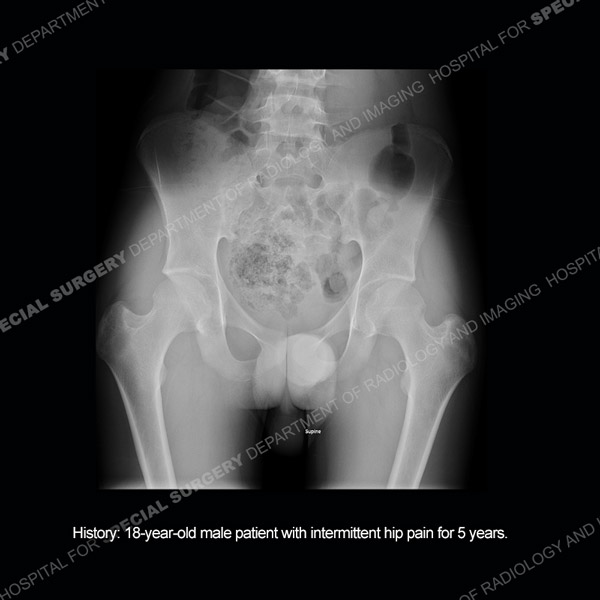

Featured Case of the MonthCase 216: 29-year-old woman with persistent left knee pain.